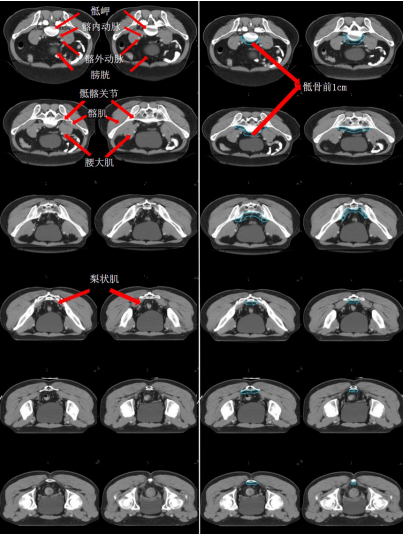

a) GTV(紅色)通過對比定位 MR 圖像,在 CT 定位圖像完成 GTV 的勾畫(圖 1)。

圖 1 直腸癌 GTV 勾畫示例

b) GTVnd(粉色) :轉移淋巴結在診斷磁共振或定位磁共振圖像顯示清楚,可參考并輔助在 CT 定位圖像完成 GTVnd 的勾畫(圖 2-圖 4)。

圖 2 直腸癌俯臥位直腸系膜區淋巴結勾畫示例

圖 3 直腸癌俯臥位骶前區淋巴結勾畫示例

圖 4 直腸癌俯臥位淋巴引流區淋巴結勾畫示例